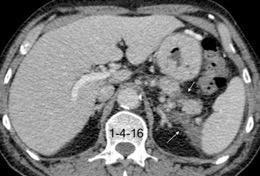

Empiema pleural secundario a carcinoma de la flexura esplénica (masa visible)

Lian R et al. Empyema caused by a colopleural fistula. Medicine (Baltimore) 2017/Osada T,, et al. Thoracic empyema associated with recurrent colon cancer: report of a case and review of the literature. Dis Colon Rectum 2001